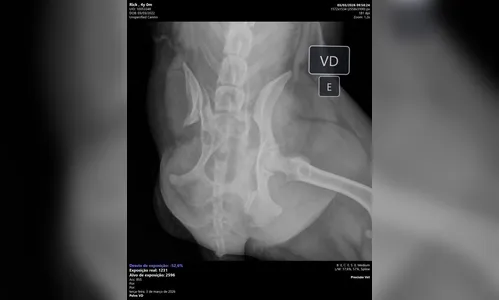

Exames realizados na clínica apontaram que o cachorro sofreu duas fraturas e está com dificuldades para se movimentar. De acordo com Angela, o animal sente dores, tem dificuldade para ficar em pé e até para fazer suas necessidades.

EXAMES:

Cão de três patas atropelado em Apucarana precisa de ajuda para cirurgia

AutorFoto: Lis Kato